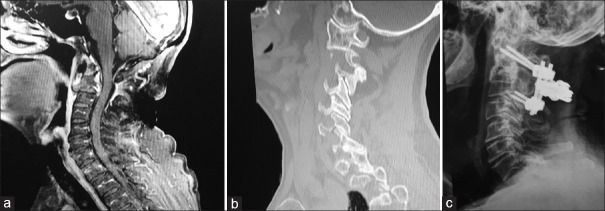

Abstract Image